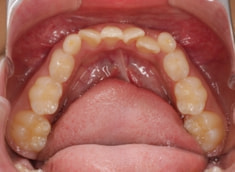

症例紹介

小児期ケース:叢生(ガタガタ)

治療法:拡大プレート+フルパッシブブラケット(クリアスナップ)

治療前